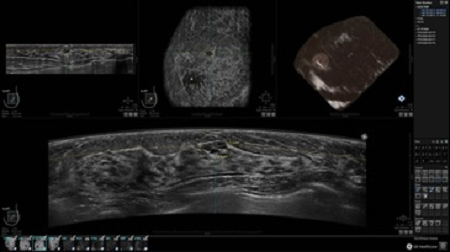

GE INVENIA ABUS – это современный УЗИ аппарат, который создан для точной и эффективной диагностики сканирования с высокой плотностью молочных желез. Выявляемость патологий раковых и предраковых стадий заболевания составляет 55%, что в конечном счете позволяет ставить врачу точные и своевременные диагнозы. Традиционные методы использования маммографии не показывают такой выявляемости, ограничиваясь лишь 3-38%.

УЗИ-аппарат GE INVENIA ABUS позволяет проводить максимально операторонезависимые процедуры, что значительно снижает риск неправильной постановки диагноза и сопутствующие издержки на обработку информации. Система готовит отчет в течение 3-х минут после сканирования, это безусловное преимущество по сравнению с обычным УЗИ сканером.

• Получение объемных 3D изображений с возможностью покадрового просмотра

• Алгоритмы обработки изображений: алгоритм однородности изображения ткани (TEA), подавление зернистости, компенсация акустической тени от соска (NSC), определение границ молочной железы (BBD), определение стенки грудной клетки

• Отображение объемных 3D ультразвуковых изображений, которые состоят из традиционных поперечных и воссозданных коронарных и сагиттальных проекций

• Многооконный просмотр: 4 - 12 изображений

• Стандартизованная ориентация изображения: «толстый срез» в коронарной плоскости; поперечная; сагиттальная плоскость; радиальный и антирадиальный поворот изображения; просмотр исключительно области интереса

• 360 ° APC - отображение области по «любой точке компаса»

• Одновременный просмотр двух изображений для сопоставления в коронарной плоскости